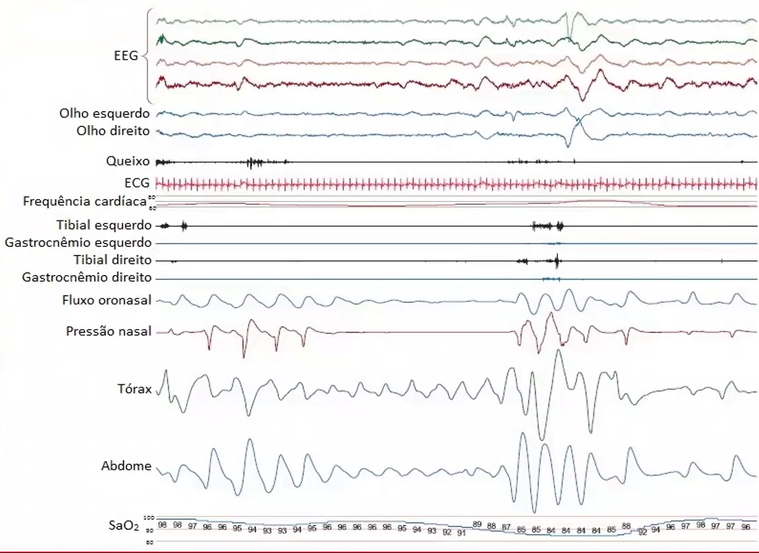

Comente os achados da PSG abaixo.

Trata-se de PSG tipo 1 ou 2. É observado um episódio de apneia obstrutiva resultando em dessaturação e despertar.